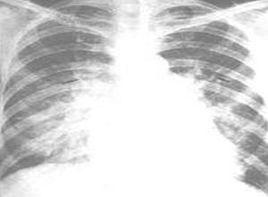

根據病史、症狀、體檢和X線表現常可對肺水腫作出明確診斷,但由於肺含水量增多超過30%時才可出現明顯的X線變化,必要時可套用CT和核磁共振成像術幫助早期診斷和鑑別診斷。

1.根據病史、症狀、體檢和X線表現常可對肺水腫作出明確診斷,但由於肺含水量增多超過30%時才可出現明顯的X線變化,必要時可套用CT和核磁共振成像術幫助早期診斷和鑑別診斷。